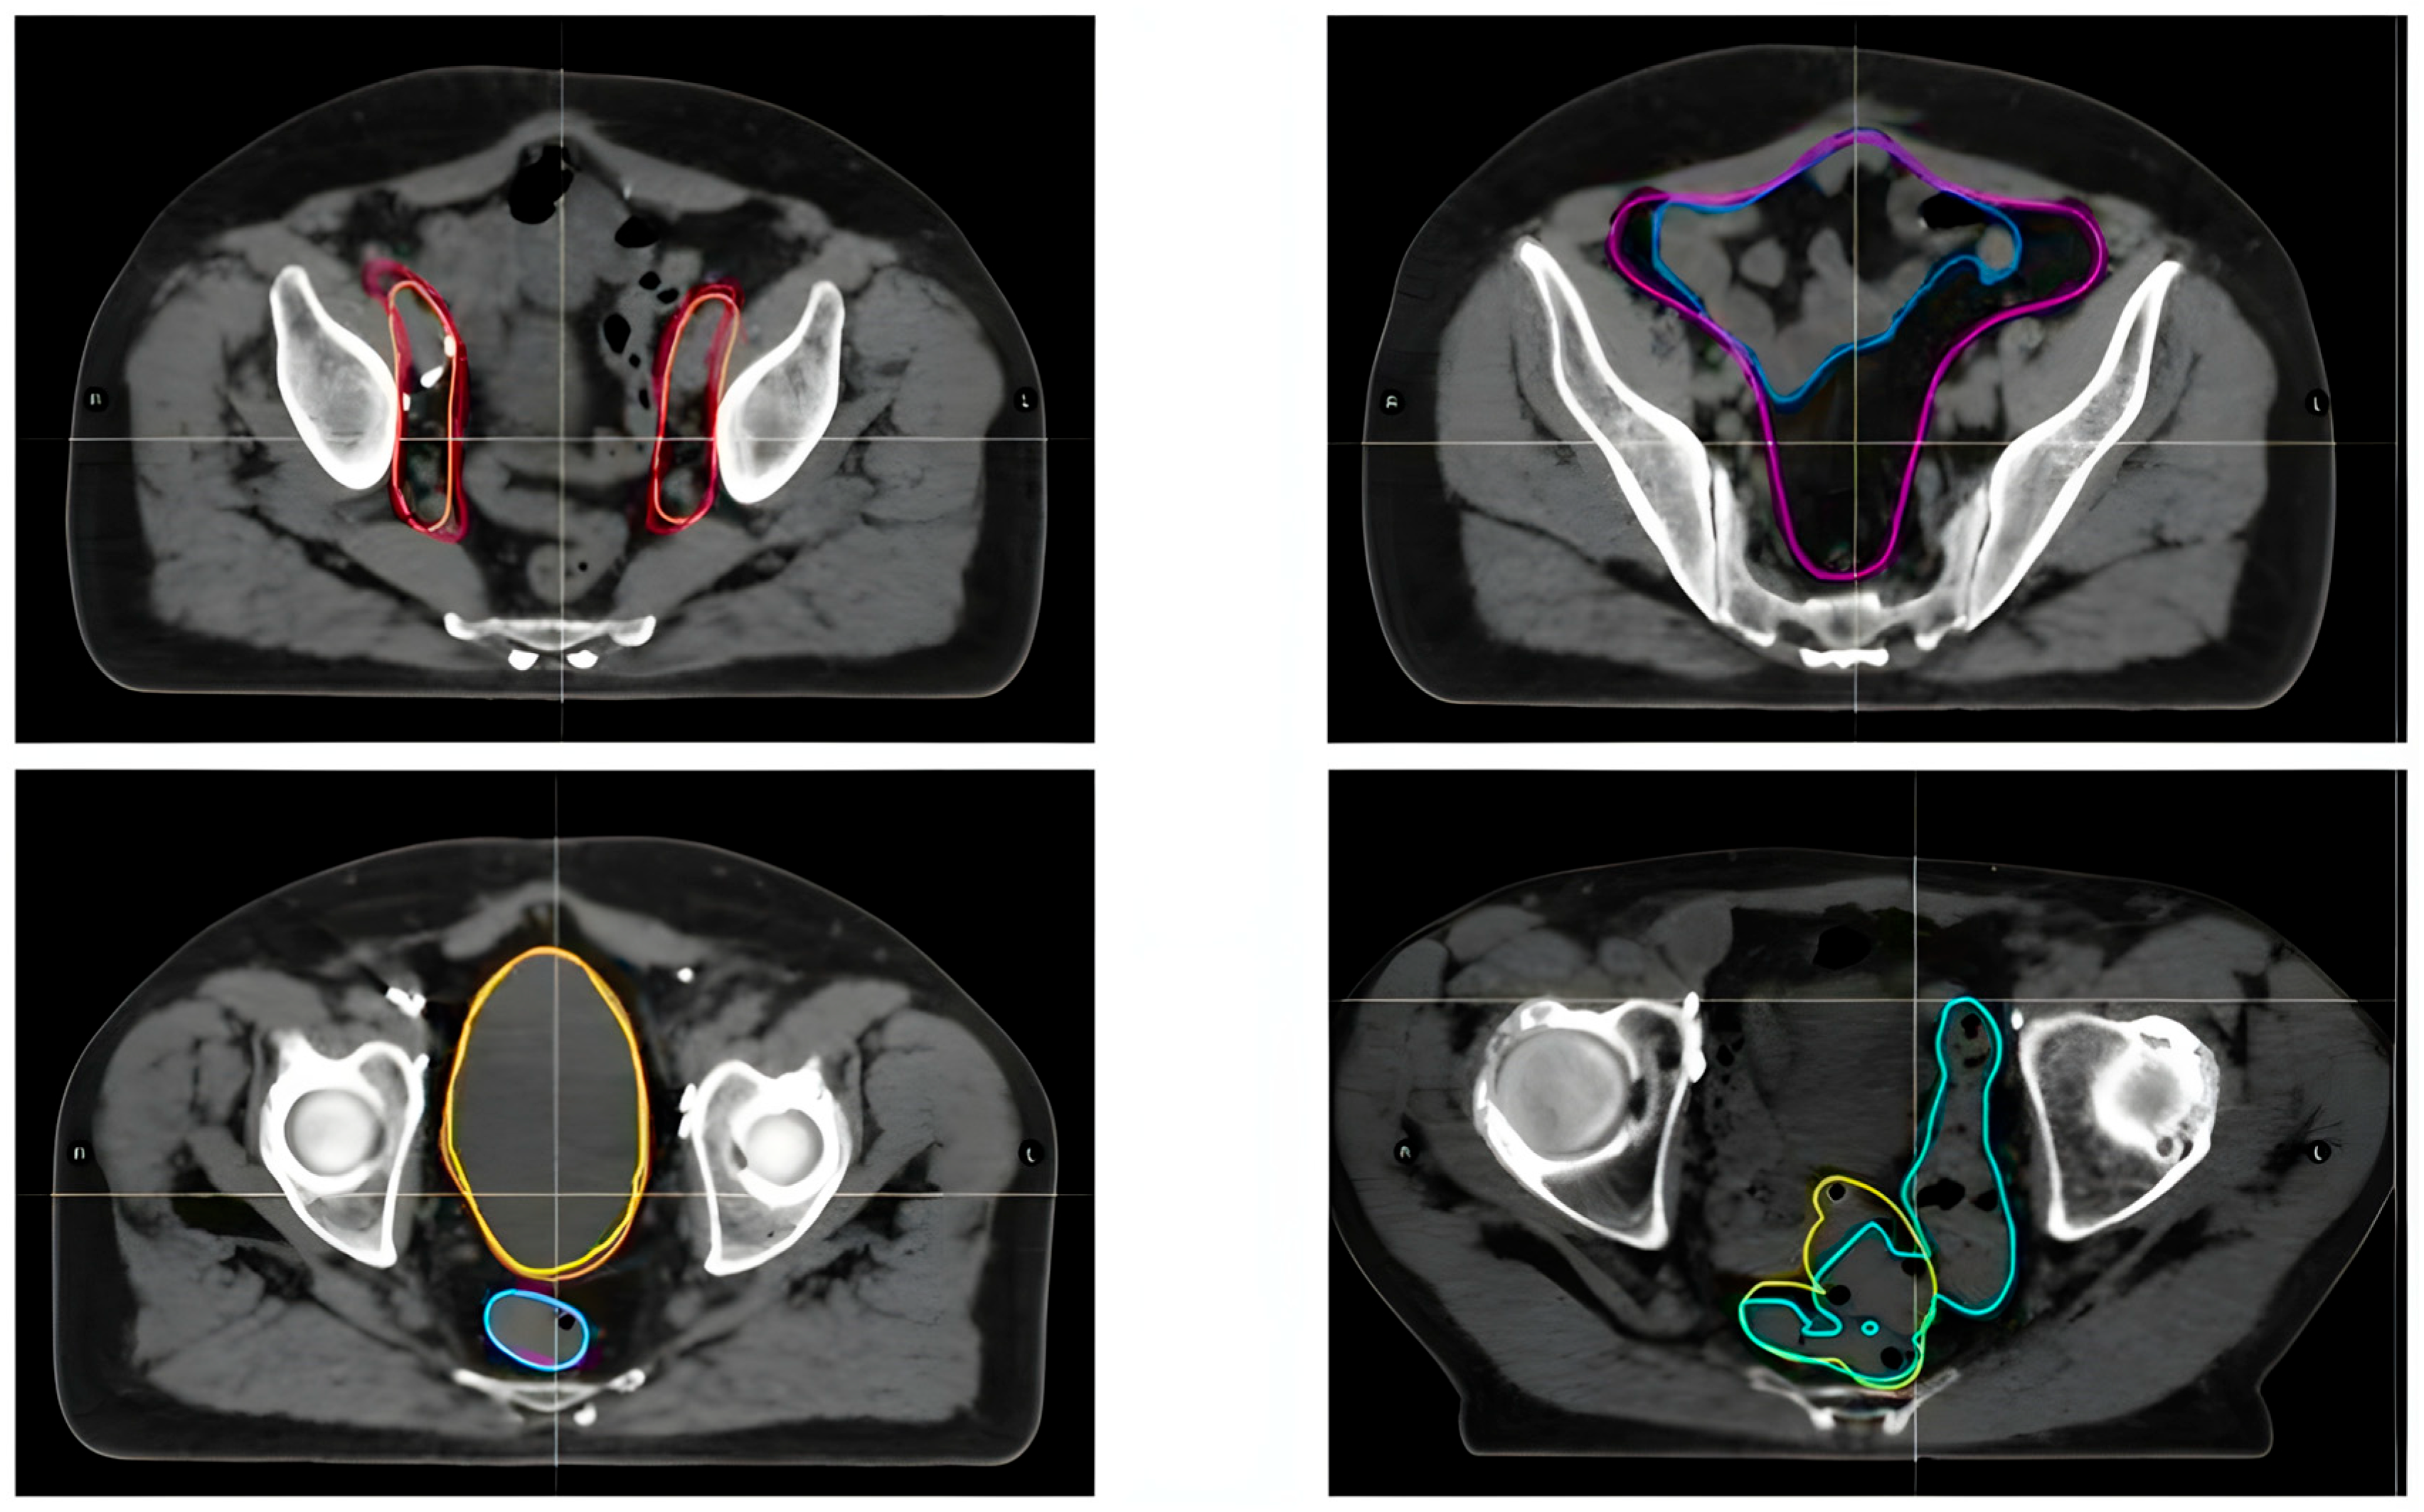

2.2. Contouring Process and Data Analysis